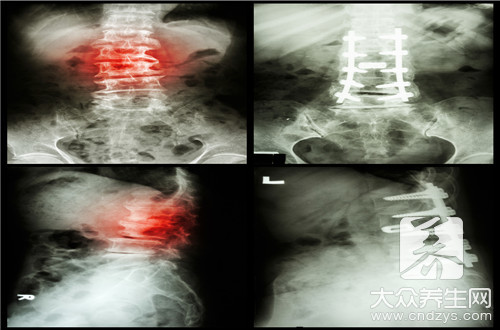

脊椎酸痛这样的现象几乎每一个人都体验过,特别是对于那些体力劳动者来说,在白天的时候,他们需要耗费大量的体力,搬抗一些重物这样是最容易造成脊柱损伤的,在第二天早上醒来就会出现脊椎酸痛,久而久之下去很可能就会造成脊椎炎,那么脊椎骨酸痛是怎么回事呢?

很多人出现脊椎骨疼都认为自己的是因为近太过于劳累导致的,其实有些人不是,有可能是因为患上某些疾病引起的,所以不要出现脊椎骨疼就单纯地认为是自己太累了导致的。

颈椎病引起的

如果您的颈椎出了问题的话,那肯定会导致您出现脊椎骨疼的,所以谨防颈椎病的出现,一旦发现了,就一定要及时调理,不然的话,只会加重您脊椎骨疼,让您的颈椎一天不如一天。

(1)颈椎第四、五、六颈椎的脊神经后支向背部延伸,支配上背部的皮肤肌肉。(2)当颈椎发生退行性改变时,如果牵拉到第四、五、六颈椎的脊神经后支,就会导致出现背痛。2、症状表现

颈背疼痛、上肢无力、手指发麻,头晕、恶心甚至视物模糊,吞咽模糊都是颈椎病的症状表现。